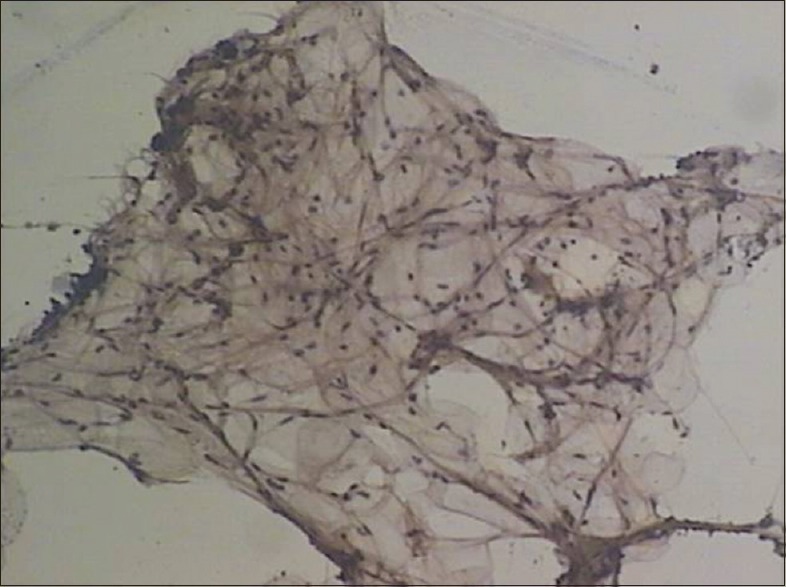

A 3-year-old female child presented with a progressive disproportionate enlargement of the second and third toes of the right foot since birth [Figure 1]. There were no history of any pain or neurovascular symptoms and also no family history of extremity gigantism. The developmental milestones were according to the age. On physical examination, there was nontender enlargement of the second and third toes of the right foot. No overlying cutaneous changes, pitting edema, or bruit was seen. All the other extremities were found to be normal on examination. A plain X-ray of the right foot was performed that revealed soft-tissue swelling involving the second and third toes with hypertrophy of the phalanges [Figure 2]. Gray-scale ultrasound and color flow Doppler revealed diffuse soft-tissue thickening, without any abnormal calcifications or abnormal blood flow. Fine-needle aspiration from the second digit yielded blood-tinged fatty aspirate. Smears examined revealed fragments of mature adipose tissue [Figure 3]. No malignant cells were identified. The background revealed fat droplets admixed with red blood cells (RBCs) and few inflammatory cells. Correlating the lesion's clinical presentation, imaging and cytological finding possibility of benign mesenchymal lesion of lipomatous origin was considered with a differential diagnosis of ML and fibrolipomatous hamartoma. Debulking surgery was performed. Histopathological examination of the sent material showed mature fibroadipose tissue involving the subcutaneous plane. The nerve sheath and the surrounding muscle fibers were free of fatty infiltration. Thus, a definitive diagnosis of ML was rendered which confirmed the initial cytological possibilities.

| Figure 3:Cytosmears reveal mature adipocytes (Pap, ×100)